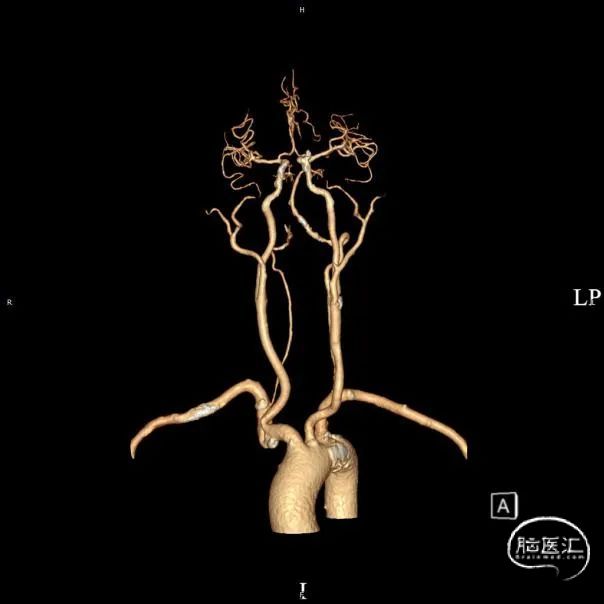

➢头颈部CTA(三维重建MIP像)

➢头颈部CTA(原始像)

患者于入院前10天突发视物重影,5分钟左右缓解,当晚18:00出现颈后不适伴左上肢持续性麻木,10天后来我院急诊神经内科就诊,就诊时测血压191/93mmHg,自行服用拜新同1粒。 完善头颅MRI:桥脑、两侧小脑急性缺血性梗塞;右侧基底节软化灶;两侧侧脑室旁少量白质疏松;老年脑改变。 入院后予药物保守并完善头颈部CTA:左侧颈内动脉虹吸段多发钙化斑块、混合斑块,管腔轻-中度狭窄,C7段小动脉瘤。右侧颈内动脉虹吸段多发钙化斑块,管腔轻度狭窄。右侧椎动脉纤细,V4段局部显示欠清。左椎V1、V2段非钙化斑块,局部管腔重度狭窄-闭塞,V4段钙化斑块,管腔中度狭窄。右侧部分型大脑后动脉,P1段重度狭窄,P2段中度狭窄。双侧大脑中动脉M2段中至重度狭窄。 告知患者病情存在进一步进展可能,患者家属商量后要求手术治疗。

术前影像考虑右侧孤立椎,左侧椎动脉V1段重度狭窄、狭窄段以远扭曲成襻且合并长节段多发动脉粥样硬化狭窄改变(夹层待排),同时左椎V4段局部重度狭窄可能;